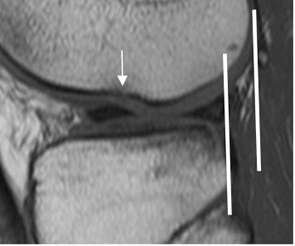

Fig 104. Signo de la línea.

RM sagital en T2. La línea trazada en la parte posterior del LCP, no cruza la cortical femoral, por aumento en la angulación del ligamento.